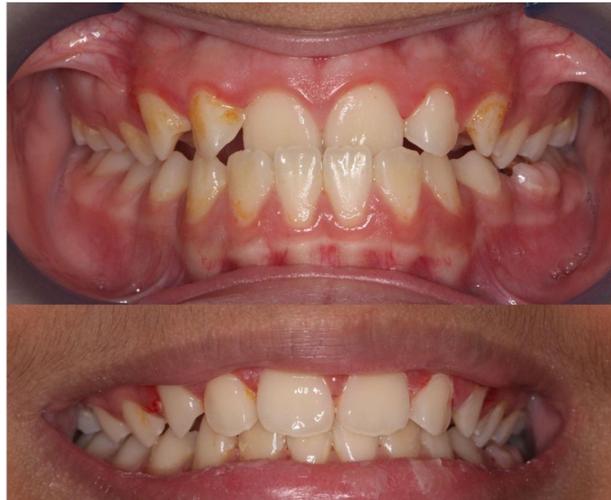

(图片来源网络,侵删) -